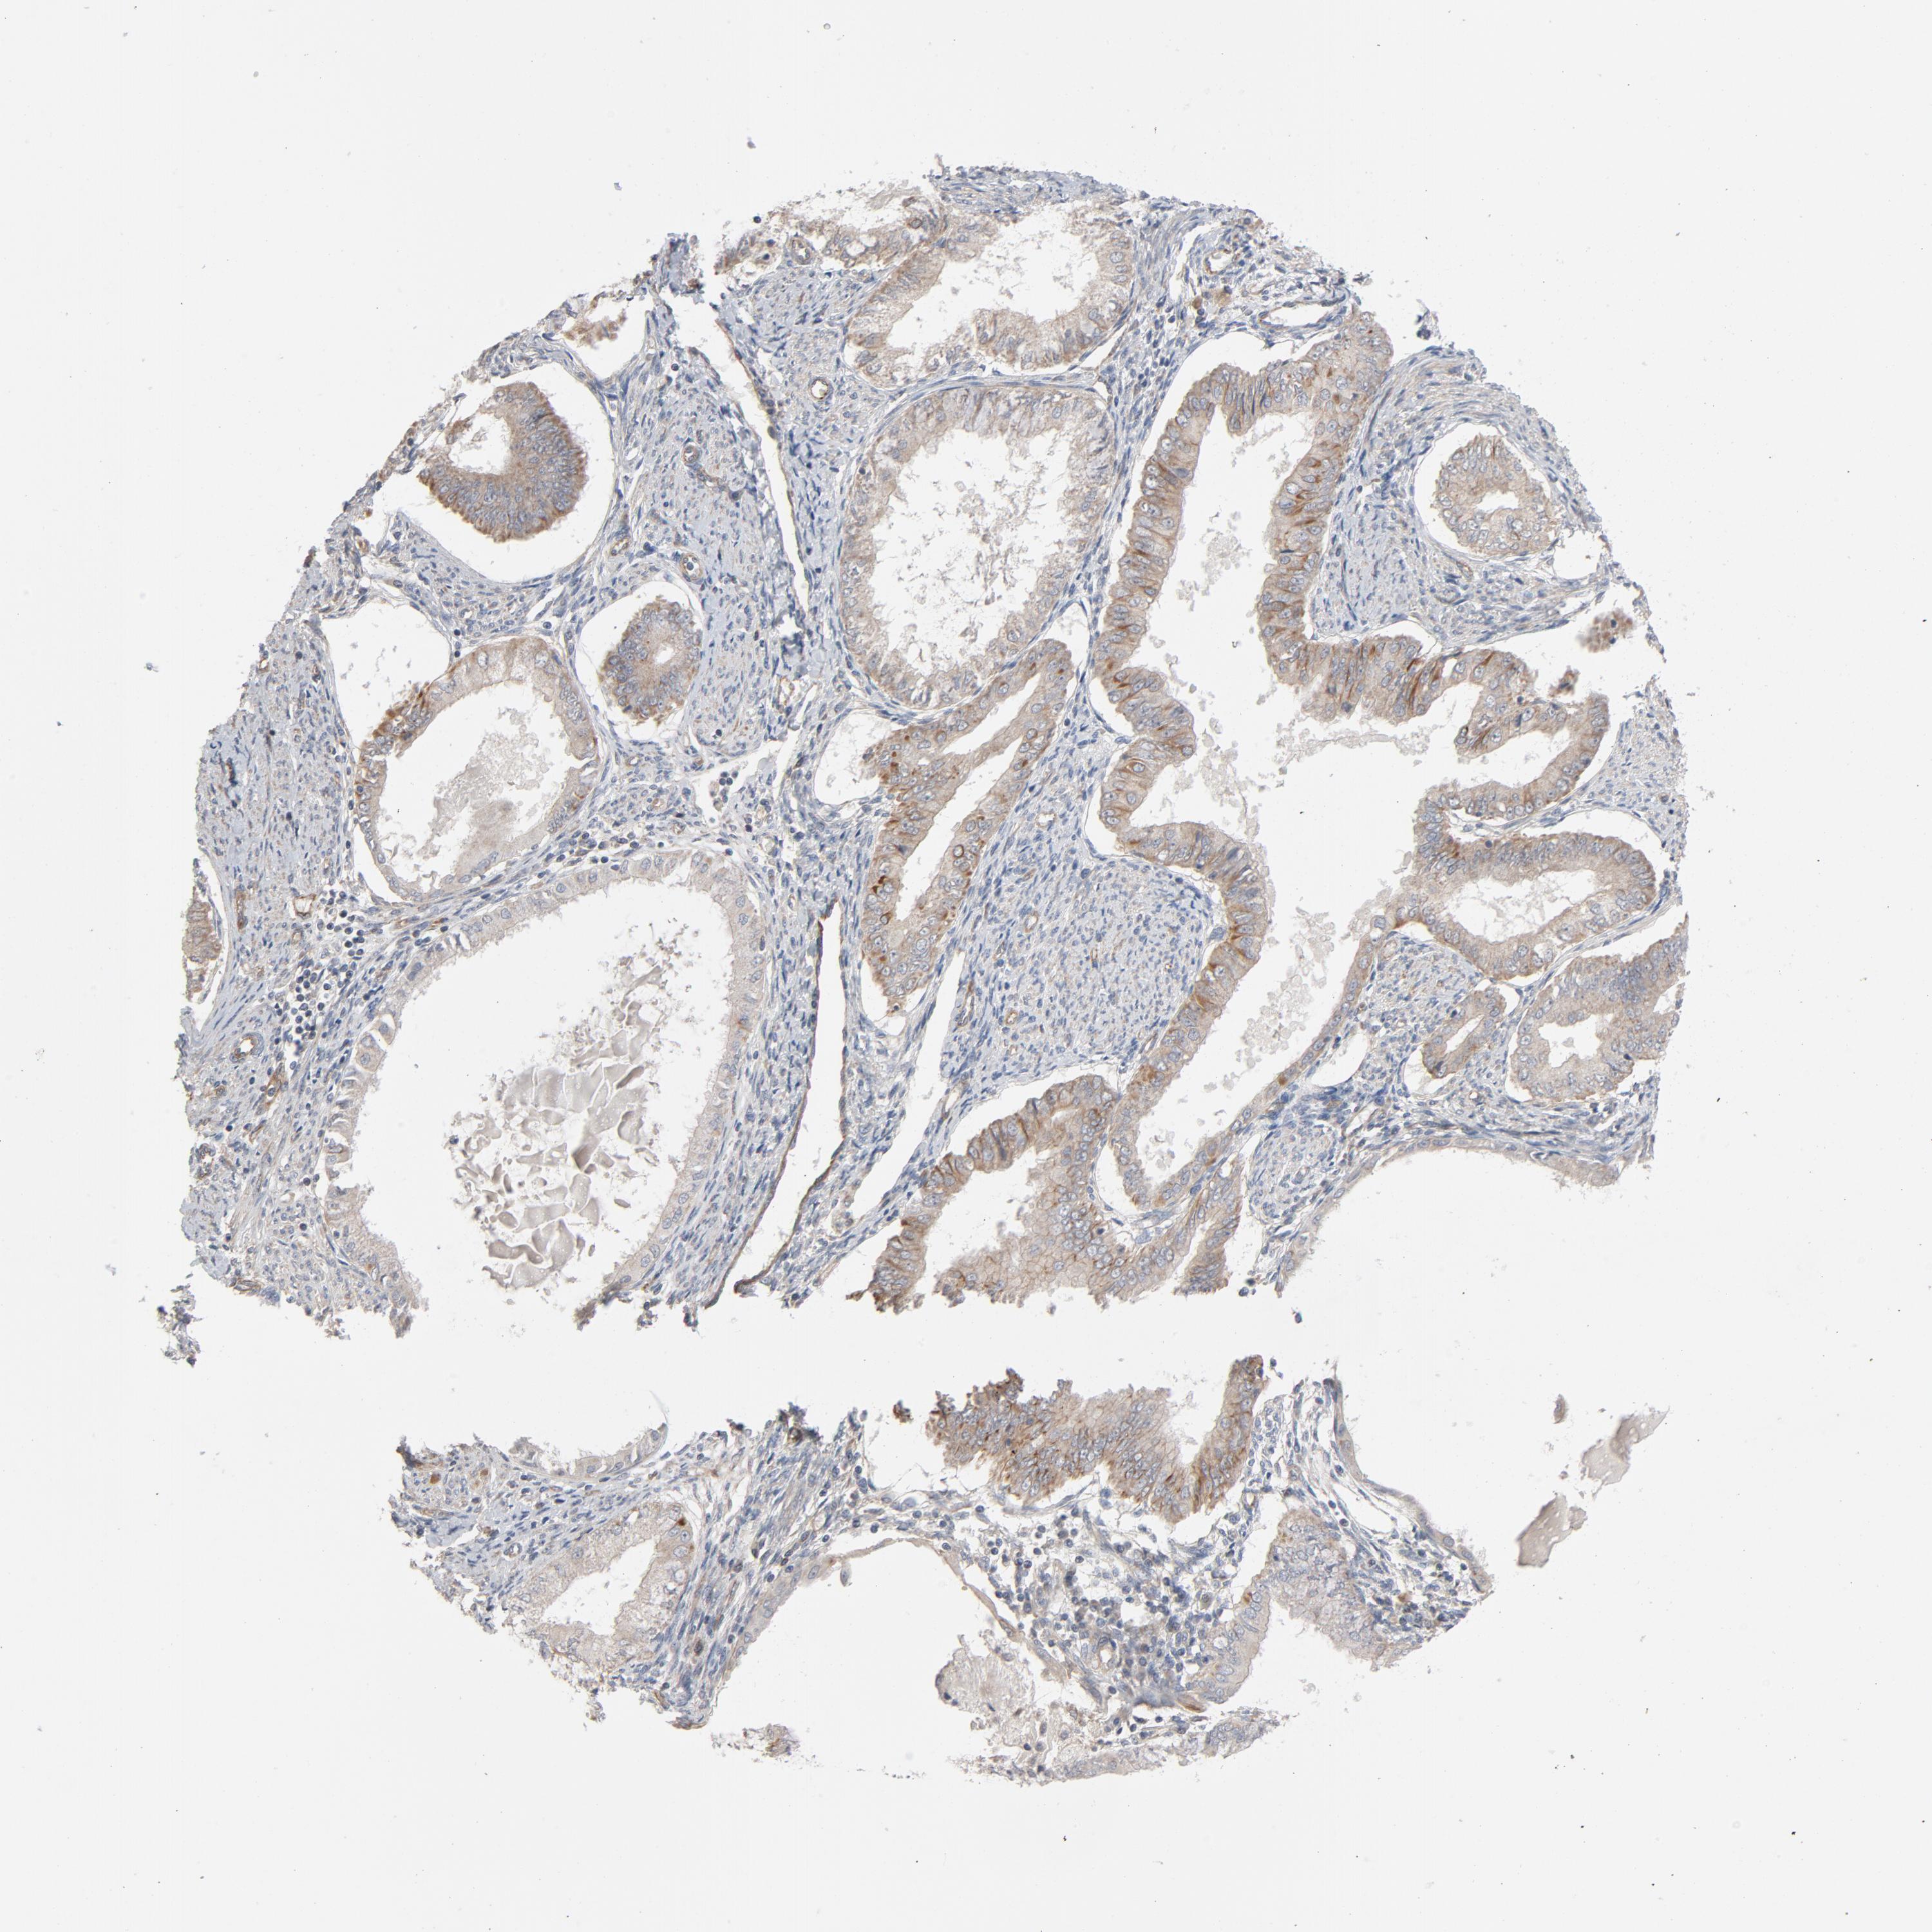

ENDOMETRIAL CANCER - Protein expressioni

A mouse-over function shows sample information and annotation data. Click on an image to view it in a full screen mode. Samples can be filtered based on level of antibody staining by selecting one or several of the following categories: high, medium, low and not detected. The assay and annotation is described here.

Note that samples used for immunohistochemistry by the Human Protein Atlas do not correspond to samples in the TCGA dataset.

Antibody stainingi

Antibody staining in the annotated cell types in the current human tissue is reported as not detected, low, medium, or high, based on conventional immunohistochemistry profiling in selected tissues. This score is based on the combination of the staining intensity and fraction of stained cells.

Each image is clickable and will lead to virtual microscopy that enables deeper exploration of all samples and also displays staining intensity scores, fraction scores and subcellular localization as well as patient and tissue information for each sample.

Antibody HPA003747

Antibody HPA019769

Staining

High

Medium

Low

Not detected

Intensity

Strong

Moderate

Weak

Negative

Quantity

>75%

75%-25%

<25%

None

Location

Nuclear

Cytoplasmic/membranous

Cytoplasmic/membranous,nuclear

Adenocarcinoma, NOS

Adenoma, NOS